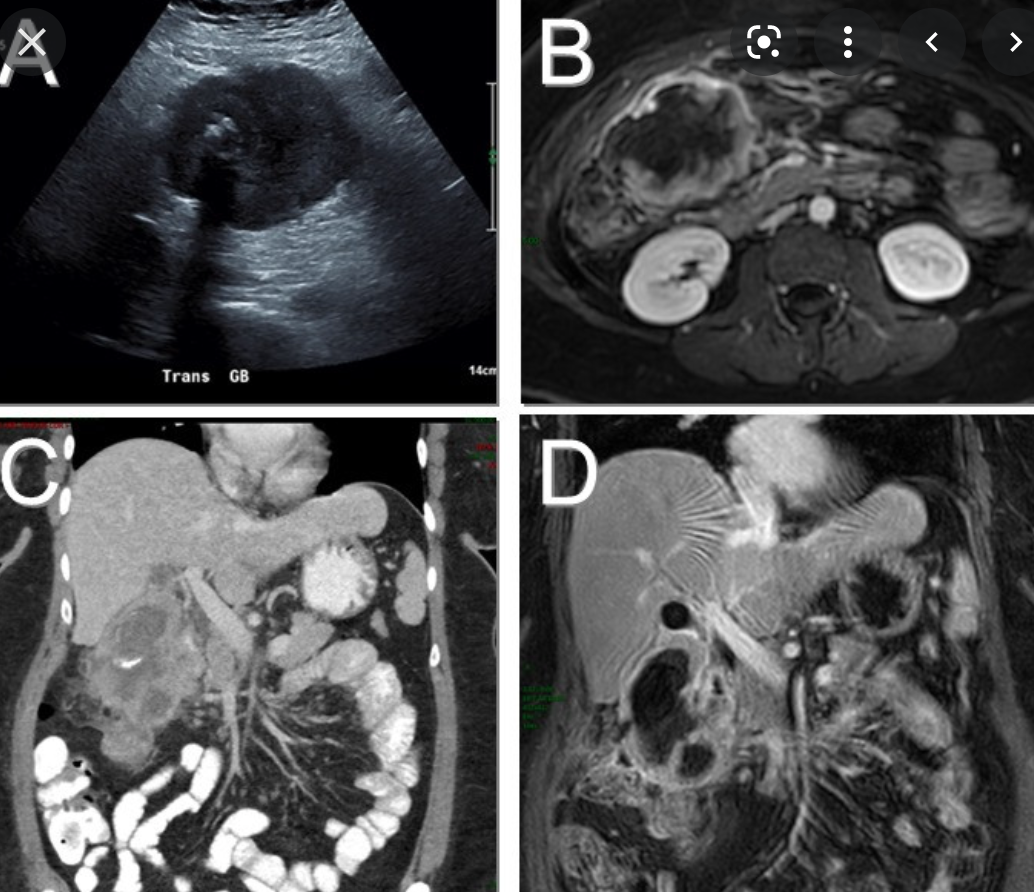

- KLATSKIN TUMOUR (image)

What is this?

Two types?

- Cholangiocarcinoma

- adenocarcinoma of the biliary tree

- Two types

- scirrhous type

- worse prognosis

- Polypoid type

- scirrhous type

- Clincal

- jaundice

- pruritus

- weigh loss

- Rx

- pancreaticodyodenecticomy (whipples)

- palliative procedures

- stent

- biliary bypass

Imaging findings of Intrahepatic Cholangiocarcinoma

where geographically is it more common?

- More common in asia than in the USA

- Adenocarcinoma from the intrahepatic bile ducts

- Biliary ductal dilatation distal to tumour

- lesions have irregular borders with infiltrative margins

- Delayed peripheral to central enhancement as a result of fibrosis and hypovascularity

- Capsular retraction and vascular invasion.